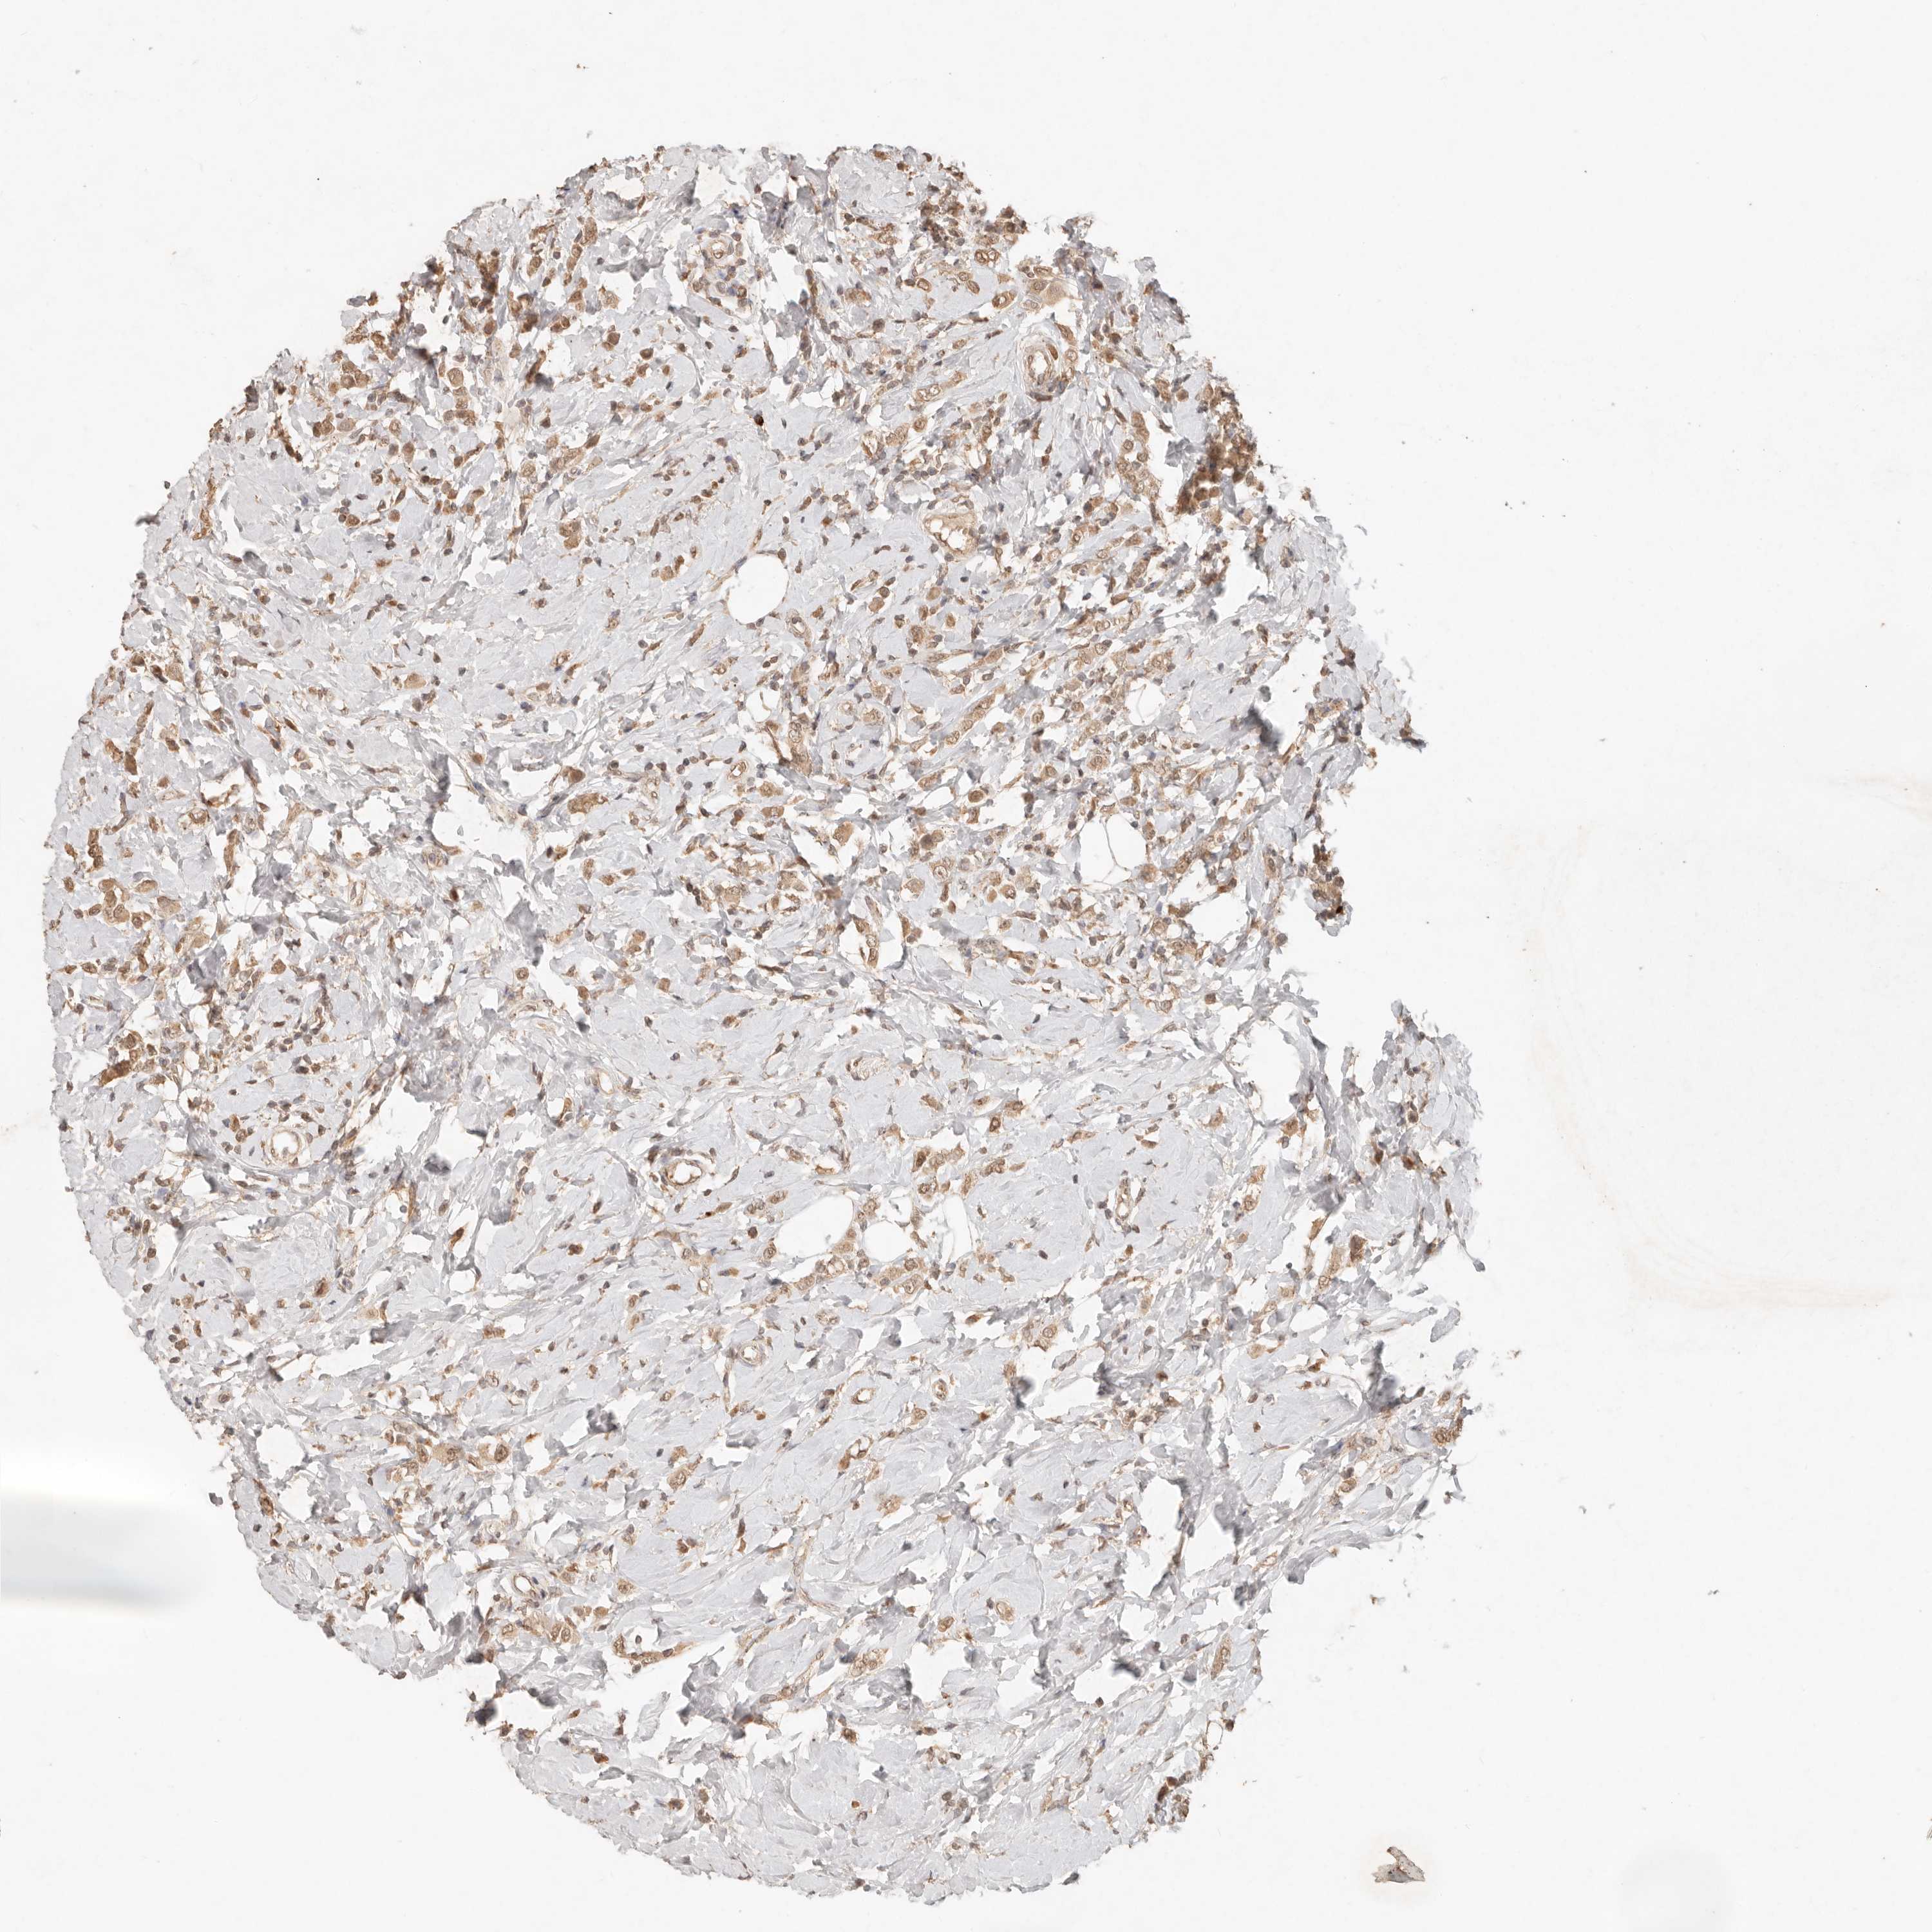

CANCER BREAST CANCER Show tissue menu

BRCA TCGA BRCA VALIDATION PROTEIN EXPRESSION

Breast cancer

Human cancer

LMO4 is not prognostic in Breast Invasive Carcinoma (TCGA)